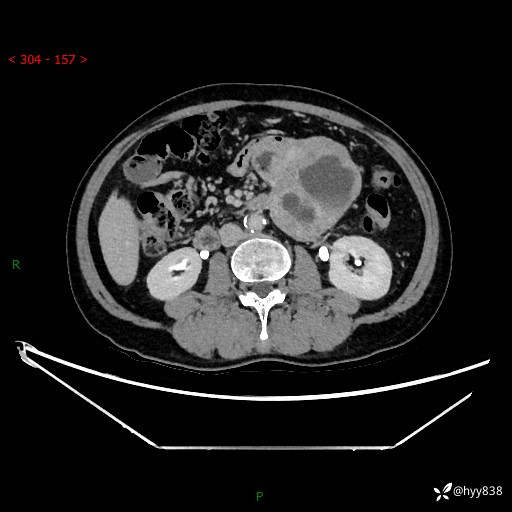

年龄:61岁

主诉:发现腹膜后肿瘤3天

腹部CT平扫+增强(动脉期+静脉期)